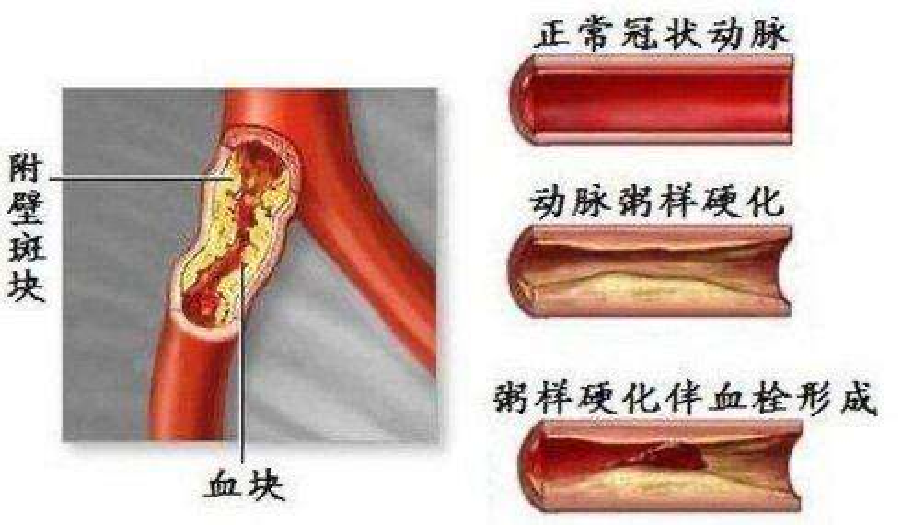

(2)钙是血管硬化的帮凶

动脉粥样硬化示意图

冠状动脉梗塞导致心肌坏死

颈动脉粥样硬化和脑梗死

血管硬化常见于高血压,高血脂,糖尿病等。

高血脂引起动脉硬化继发各种疾病

这张图提示,高血脂是导致动脉粥样硬化的元凶,这个理念已经广为人知,深入人心。但却忽略了另一个导致动脉粥样硬化的因素,那就是高同型半胱氨酸血症。它是一个隐藏得很深的幕后元凶,很多体检中心的项目里就不包括同型半胱氨酸。

动脉粥样硬化虽然是中老年人的常见病和多发病。但血管粥样硬化的形成并不是一蹴而就的,而是冰冻三尺非一日之寒的结果。现在动脉粥样硬化的发病有年轻化趋势,这当然跟日常的生活方式有关。比如喜吃高热量食品而又不好运动的人,发病率高。同型半胱氨酸是蛋白质中蛋氨酸代谢的中间产物。如果每天摄入蛋白质太多,一时半回儿消化不了,就会导致同型半胱氨酸堆积,导致指标超高(≧10μmol/L)。同型半胱氨酸会激惹动脉血管内皮,造成内皮细胞损伤,引发血管局部炎症,最终导致这段动脉血管壁出现粥样硬化斑块。

当血管壁的内皮细胞受到高血压的冲击,高血糖,高尿酸、高同型半胱氨酸和低密度脂蛋白胆固醇等不良因子的长期刺激,血管内皮就会发炎。我们经历了三年的新冠疫情,大家都知道发炎就是身体免疫发生反应。新冠是病毒的入侵引起身体的免疫炎症反应。而血管壁发炎却是由于我们自身的代谢产物刺激而出现的炎症反应。离子钙具有“哪里有炎症,就到哪里去沉积”的特性,当血管壁出现炎症,离子钙当然也要来插上一杠子。脂质斑块与离子钙的结合就在血管壁上结成厚厚的一块硬疙瘩。就如同把煮粥煮成的糊锅吧贴在动脉壁上一样,所以取名动脉粥样硬化。

动脉粥样硬化当然会造成血管狭窄,甚至发生堵塞。如果只是阻塞小的血管,不重要器官的血管倒不致命,只是血脉不通,总感到疼痛不适。常言道:通则不痛,不通则痛。但如果是至关重要的血管发生阻塞,那可就要了命了。